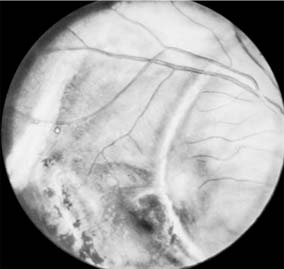

Figure 19-3

Figure 19-3: Hole in retina, macular area, posttraumatic.